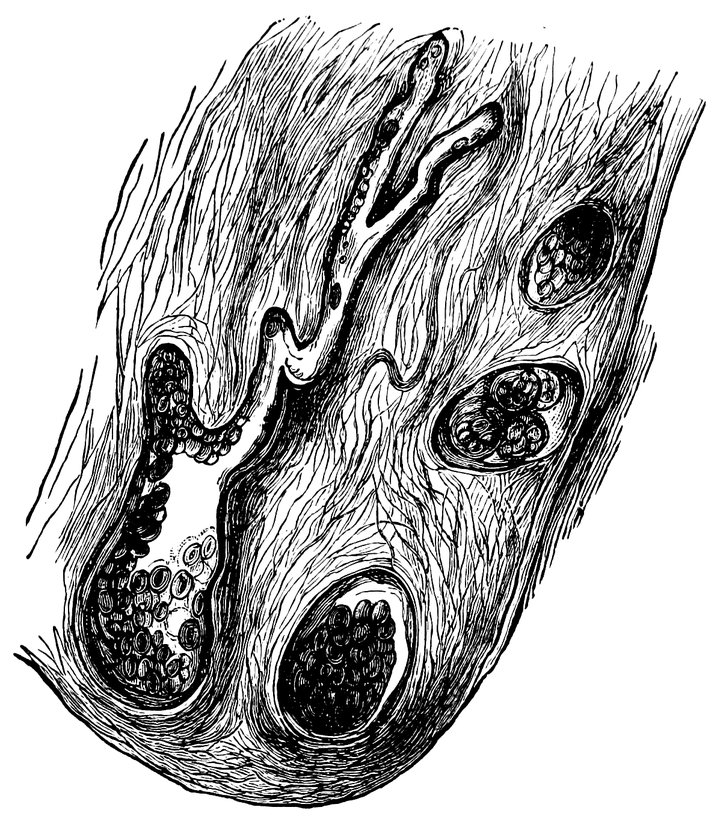

We must first consider the changes in the ovaries, which play an etiologically important part. At the onset of puberty, the follicular masses of the ovary exhibit a more active growth, the follicles increase in size, with their contained ova they approach the surface, and finally, by the bursting of the follicles, the ova are extruded. Then, in the life-phase in which conception occurs, and under the influence of the hyperæmia of all the pelvic viscera that accompanies this process, a notable development of the corpus luteum takes place, this latter body reaching its maximum size in the eleventh week of pregnancy, subsequently undergoing involution and leading to the formation of a considerable scar. Finally, in the critical period of life in which the menstrual flow ceases, a continually increasing growth and new formation of connective tissue-stroma takes place in the ovaries at the expense of their cellular constituents, and a regressive metamorphosis of the graafian follicles occurs.

In association with these sexual processes there ensues a series of striking changes in the shape and consistency of the ovaries, affecting both the surface and the parenchyma of these organs, and capable of stimulating the nervous ramifications in their tissue. In this connection it is worthy of note that the branches supplying the ovaries from the spermatic plexuses of the sympathetic contain a considerable proportion of sensory fibres.

10At the time of puberty the infantile uterus undergoes changes affecting both its external form and the shape of its interior cavity. The body of the uterus enlarges to the size characteristic of sexual maturity, and its mucous membrane becomes the seat of periodic changes. This waxing and waning growth and transformation of the uterine mucous membrane continues throughout the period of menstrual activity, the most superficial layers of the membrane being shed during menstruation, a process followed by regeneration, which is itself succeeded by the premenstrual thickening. When conception occurs, still more extensive changes ensue, the fertilized ovum becoming imbedded in the uterine mucous membrane, and the pregnant uterus, in shape and structure and in the respective relations of the body and neck of the organ, in the increasing distension of its veins and the increasing size of its nerves, becoming adapted to the important functions it has now to fulfil. When these have been fulfilled, and, parturition having taken place, the uterus is empty once more, the organ again adapts itself to altered circumstances by the process of involution. Later, in the climacteric period, a slow regressive process occurs, the outward manifestation of which is the cessation of the menstrual flow, characterized anatomically by atrophy of the muscular tissue of the uterus and of its vascular apparatus, by the dessication of its mucous membrane, by obliteration of the lumen of the uterine cavity, and ultimately by senile degeneration and atrophy of the now entirely functionless organ, so that it becomes an insignificant, cicatrized, solid body.